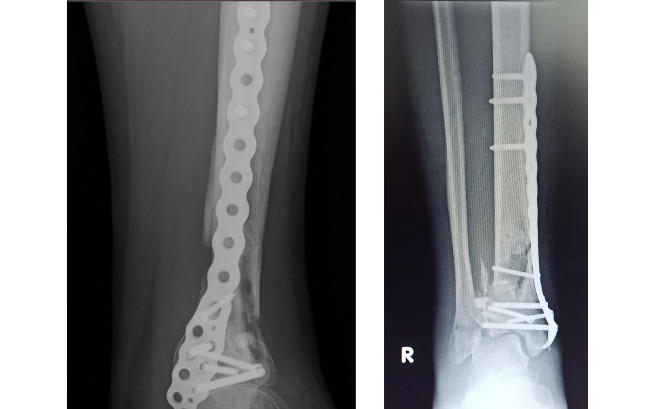

Tamtego dnia padał deszcz. Miłosz był w pracy i starał się zejść po drabinie. To trwało zaledwie sekundę. Poślizgnął się i spadł na ziemię z 10 metrów! Upadek z takiej wysokości spowodował u niego poważne złamanie kości piszczelowej prawej i uszkodzenie stawu skokowego.

Po operacji wystąpiło niestety mnóstwo komplikacji. Niewygojona szczelina złamania szerokości około 5,5 mm, nierówna powierzchnia stawowa piszczeli, ubytki kości…

Miłosz trafił na kolejną operację, jednak nie przyniosła ona efektów. Kość dalej nie chce się zrastać, a staw skokowy uległ jeszcze większej dekonstrukcji…